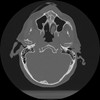

11 HUESO,,Axial,2.0,HUESO,,